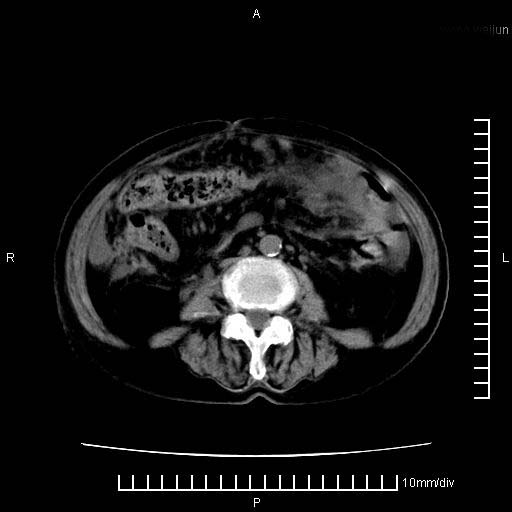

标题: CT28280:腹部增强:女性,80岁

上腹疼痛月余,外院核磁诊断胰腺癌。现临床示右下腹可明显触及包块,可片子上怎么没有看到?

胰腺结构模糊,胰尾部见囊性包块,周围脂肪密度增高,左肾前筋膜增厚,胸水、腹水。不符合胰腺ca伴腹膜腔转移。考虑胰腺炎伴假性囊肿形成、胸腹腔积液。

右肾盂囊肿。

1)考虑胰腺癌并胰腺假性囊肿形成。2)肝内低密度灶,不排除转移。3)右肾盂积水。4)腹水。5)右侧胸腔积液并右肺下叶部分膨胀不全。